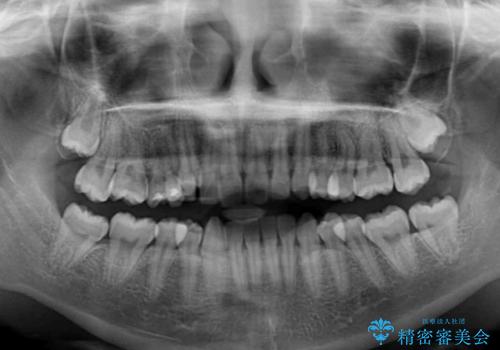

- 八重歯を気にして来院された患者様です。

本来であれば八重歯の隣後方の歯を抜歯するのですが、その後ろの歯が乳歯であり後続永久歯もなかったため、乳歯を抜去することとしました。

前から5番目の乳歯は、後続永久歯である小臼歯と比べて幅径が大きいため、移動に時間がかかりましたが、きれいに仕上げることができました。